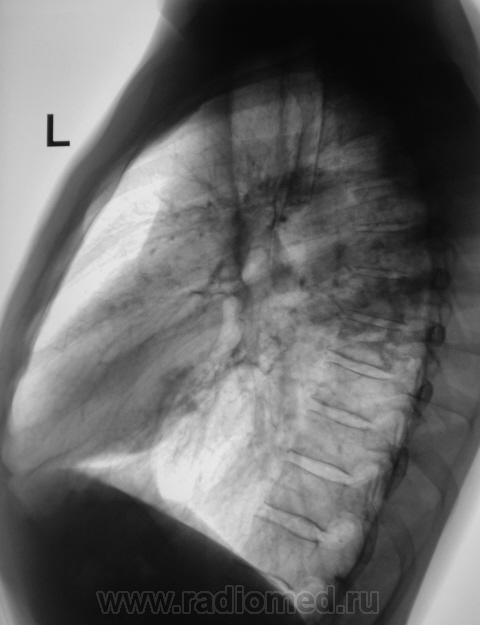

Пациент направлен на рентгенографию органов грудной полости с диагнозом - "Бронхит".

Пациент направлен терапевтом на рентгенографию органов грудной полости с диагнозом - "Бронхит".

Ваше мнение коллеги?

Процесс 2х сторонний, судя по интенсивности "не первой свежести" похоже на туберкулез, хоть не типичная локализация.

Туберкулез, без сомнения. О его форме и стадии без анамнеза судить затруднительно. Возможно, 2-х сторонний инфильтративный в ф. рассасывания, уплотнения, формирования плотных очагов. Ранее "наплевал" себе в язычки.

туберкулез.конечно,есть типичная локализация,однако намерен пробратьсяи туда.где ему совсем не место,что бы нас запутать.

Да, в последнее время, все чаще и чаще, имеются ссылки на наблюдения, свидетельствующие о не типичной (верхушечной, в верхних отделах) локализации туберкулёза.

Разве в представленном случае нетипичная локализация ТБС? Аксиальный субсегмент, SII,SVI? Типичные бронхогенные отсевы в язычки?

"Шестерка", конечно, типичная локализация, подмышечный субсегмент, конечно тоже, но вот "верхушки"?

Есть же статистика по частоте поражения туберкулезом того или иного сегмента. Верхушки поражаются чаще, но не в 100%. Где тонко, там и рвется (focus minoris resistentae).

Меня не покидают сомнения, что "это" - не туберкулёз?

Мы вместе с коллегой фтизиатром долго сидели над этими снимками. Решили провести "противовоспалительное лечение", и провести контроль.

Архив. Флюорограмма прошлого года - "норма"

верхушки,а так же все задние сегменты(2.6,,реже 10)наиболее типичная локализация туберкулеза,субплеврадьно.И если год назад была норма,это еще не не значит,что это не туберкулез,а поможет только в определении активности процусса.

Спасибо коллега за коммент. Вот, мы с коллегой фтизиатром, взвесив все "за" и "против", решили в течение 1 - 1,5 недель провести противовоспалительную терапию, а затем "решать вопрос". Архив, а именно, отсутствие изменений в прошлом году, также было учтено.

Пациент получает противовоспалительную терапию. Но, прибегает коллега фтизиатр - "палки", "палки", "палки"...

Берем на "контрольное" обследование перед госпитализацией в областное специализированное учреждение...